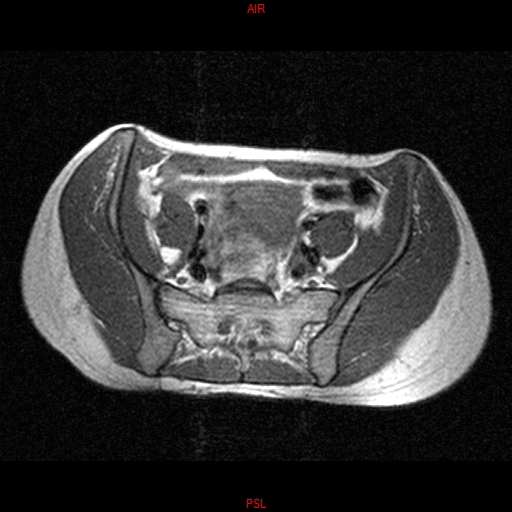

• RESONANCIA NORMAL SACROILIACAS  AXIAL T1